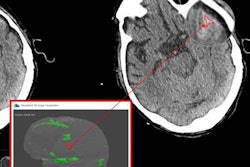

The deal will allow TriHealth of Cincinnati to update its PACS infrastructure and incorporate AI applications for medical imaging into its system, it said. TriHealth will also adopt IBM Watson Imaging Clinical Review, a tool that analyzes electronic medical record information.